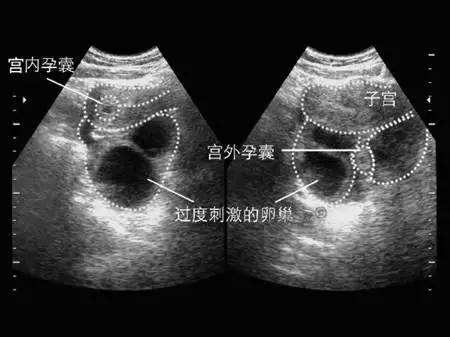

大家都知道,一般情况下,胎儿是在母体子宫内生长发育的,对于胎儿来说才能正常生长,然而,由于某方面的原因发生了宫外孕,是很危险的,那么,宫外孕感觉痛的位置在哪?

停经:异位妊娠的早期症状很容易与正常的早孕反应相混淆,如果孕妇在短时间内身体出现停经及早孕反应外,有时候还会出现一侧的下腹胀痛,检查发现输卵管正常有肿大,应怀疑为异位妊娠。